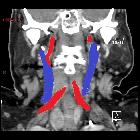

Retropharyngeale

"Kissing Carotids" in der Computertomografie axial, koronar, sagittal und Volumen Rendering. Die elongierten Karotiden treffen sich medial retropharyngeal.